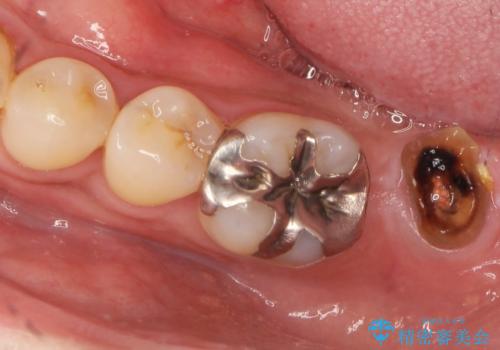

- 長期間放置してしまった虫歯の治療を希望され来院されました。

・重度虫歯による残根状態・欠損歯→インプラント補綴

・対合歯の欠損による歯の挺出→マイクロインプラントを用いた小矯正を行うことで咬合平面を是正

噛み合う歯が欠損し長時間放置すると、歯が挺出(歯が伸びてくる)し欠損補綴を行おうにもスペースが足りない場合があります。(クリアランスの不足)

加えて咬合平面の乱れを放置したまま無理やり補綴治療を行うと、特定の部位に過大な力がかかり当該歯を痛めてしまうこともよくあります。

今回、左下6は頬側歯頚部に虫歯があり圧下を行ったことからクラウンにより補綴を行いました。